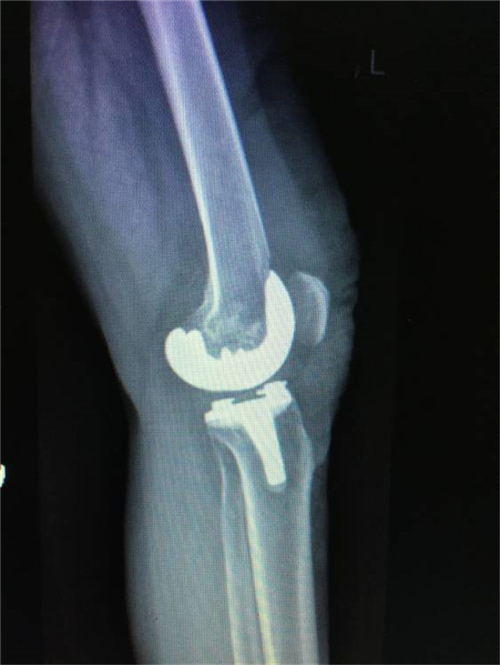

经过与家属的耐心沟通,谭宜昌主任及其团队决定为谢某实施膝关节置换手术。8月25 日上午,谭主任及其团队历时90分钟,成功为患者实施了膝关节置换术。术后患者的膝关节畸形矫正,膝关节稳定性也已恢复,膝关节功能明显改善。出院时谢某脸上洋溢着满意的笑容,说非常感谢谭主任团队把折磨自己多年的疾病给治好了。

术后X线